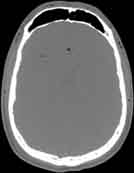

Visible Human male: Sectio transversalis 1071

CT